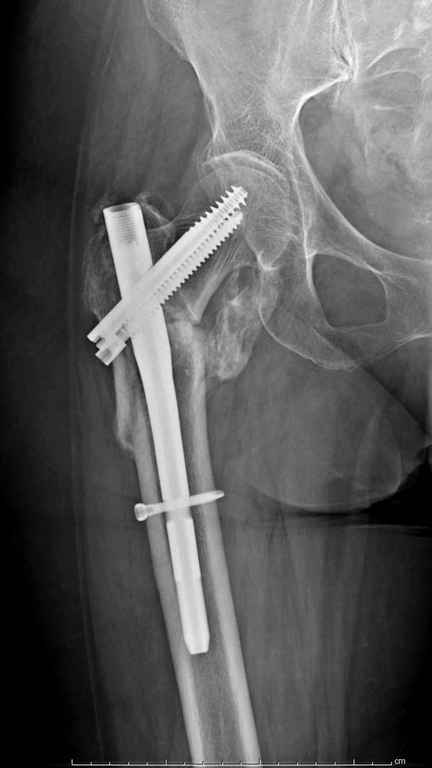

А что тут заставляет сомневаться? Здесь настолько очевидно предпочтителен закрытый интрамедуллярный остеосинтез реконструкционным стержнем (проксимальные гвозди толстоваты для такого молодого возраста), что закрадывается мысь о каком-то подвохе.

Не солидно экономить на пленке, это не делает чести презентации. Такие ограниченные нестандартные снимки приводят к тактическим ошибкам.

Предугадать распространение линий перелома при чрезвертельных и оскольчатых переломах трудно, поэтому для принятия правильного решения рекомендуется Компьютерно Томографические исследование.

При отсутствии КТ, снимок на вытяжении поможет увидеть общую картину расположения отломков, особенно потенциальные места введения импланта. Риск раскола в этом случае огромный, поэтому больной должен быть дообследован.

А так для лечения оскольчатых переломов подходят все методы, включая интра- и экстрамедуллярные в зависимости от опыта и наличия импланта.

Здесь пара похожих случаев.

Увожаемый коллега,мое мнение:фиксация и\медул.блок. стержнем Gamma-long "STRYKER". Вероятно, закрыто сделать полностью может не получится. Откроетесь на 6-8 см. для репозиции промежуточного фрагмента, но только после установки стержня. Удачи!!!